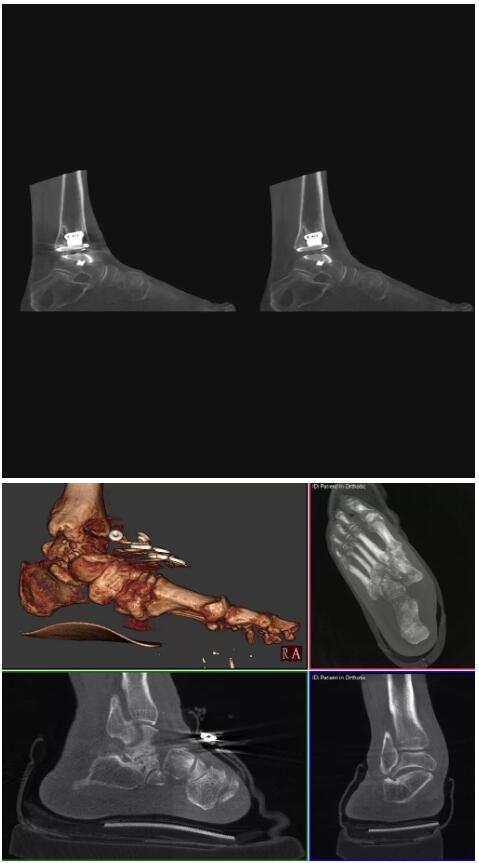

比如上面這款專用于足部和踝部掃查的CT成像系統(tǒng),患者在進(jìn)行CT掃查時(shí)只需要站在上面即可,雙腳站或者單腳站都可以,當(dāng)然,如果患者不是那么方便站著做完CT掃查,也可坐在上面。

這款CT掃查系統(tǒng)自帶屏蔽裝置,它的體積非常小,僅需要極小的空間即可,并不像常規(guī)CT那樣需要一間單獨(dú)的檢查室。此外,這種CT掃查的速度非???,僅需30秒左右可以完成檢查,輻射劑量相對(duì)常規(guī)的CT要少許多,尤其適合醫(yī)院的骨科使用。

而患者站著做足部或者踝部做CT檢查還有個(gè)好處是,可以檢查患者在負(fù)重的情況下,骨關(guān)節(jié)的真實(shí)情況,而躺著做CT掃查時(shí)未必能看出來(lái)。負(fù)重CT掃查特別是對(duì)于受傷的運(yùn)動(dòng)員或者舞蹈員來(lái)說(shuō)意義更大,能夠更準(zhǔn)確地評(píng)估傷情,幫助他們盡早復(fù)原。

以下是這些“特立獨(dú)行”的CT所拍出來(lái)的圖像: